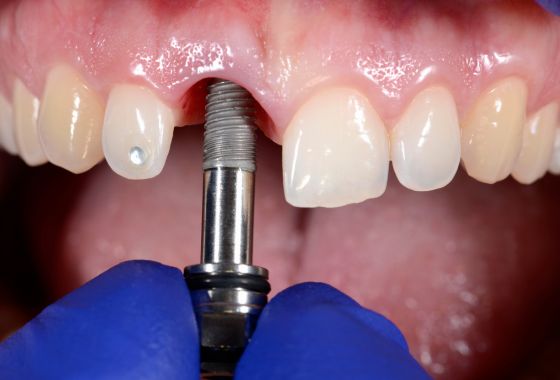

- Implantes dentales